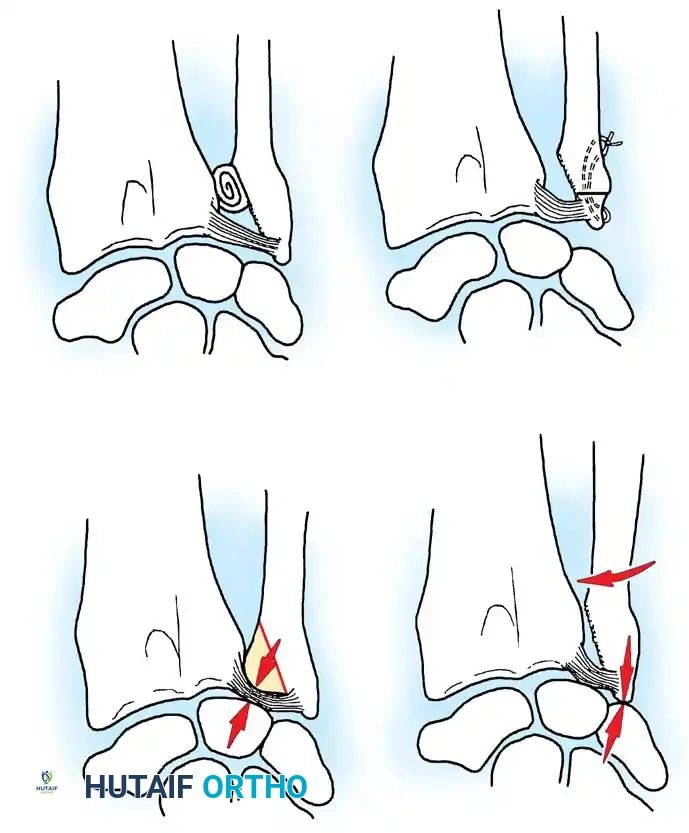

Palmer revolutionized the understanding of TFCC pathology by categorizing lesions into traumatic (Class 1) and degenerative (Class 2) groups.

Class 1: Traumatic Lesions

These typically result from forced forearm rotation or axial loading, often associated with distal radius fractures.

* 1A: Central perforation of the articular disc (avascular zone).

* 1B: Ulnar avulsion (with or without ulnar styloid fracture). Involves the highly vascularized periphery.

* 1C: Distal avulsion (involving ulnocarpal ligaments), leading to volar ulnar carpal "sag."

* 1D: Radial avulsion (with or without sigmoid notch fracture).

Illustration of various TFCC tear patterns and their respective biomechanical implications for DRUJ stability.

Class 2: Degenerative Lesions (Ulnocarpal Abutment Syndrome)

These lesions represent a continuum of wear, typically seen in ulnar-positive wrists.

* 2A: TFCC wear (thinning without perforation).

* 2B: TFCC wear + lunate/ulnar chondromalacia.

* 2C: TFCC perforation + lunate/ulnar chondromalacia.

* 2D: TFCC perforation + chondromalacia + lunotriquetral ligament perforation.

* 2E: All of the above + ulnocarpal arthritis.